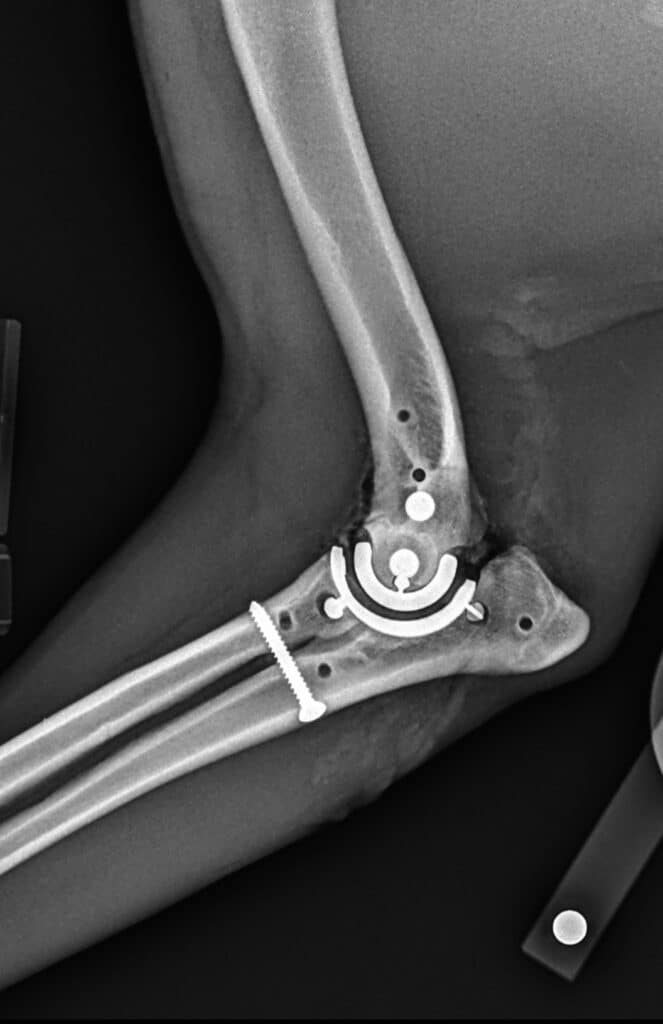

Développée pour pallier les limites des traitements traditionnels, la prothèse TATE de troisième génération se distingue par son design non cimenté et semi-contraint. Elle repose sur une stabilité mécanique obtenue par la géométrie des composants et le maintien des tissus mous environnants. L’objectif est triple : réduire les complications, simplifier la pose, et optimiser l’intégration osseuse.

- Une approche chirurgicale moins invasive

- Un risque infectieux réduit, en l’absence de ciment

- Une meilleure répartition des contraintes grâce à une conception anatomique